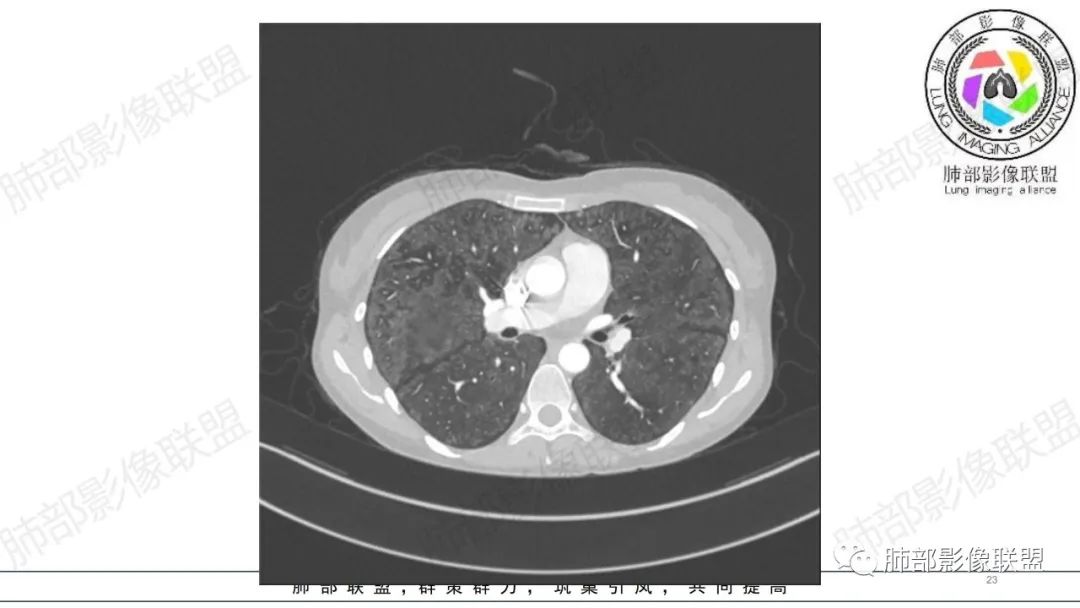

影像资料

34岁女性患者,“哮喘”病史30年,近期有可疑刺激性气体吸入史;因乏力半年,咳嗽、憋气、发热4天就诊;6.1CT提示双肺广泛毛玻璃影及粟粒样结节,胸膜下闲置及血管周闲置,可见树丫征,部分小叶间隔增厚。考虑:1.过敏性肺泡炎,有可疑刺激气体接触史,胸膜下闲置,广泛毛玻璃影,地图样分布,粟粒结节边界模糊,支持过敏性肺泡炎,但糖皮激素治疗效果不佳,且动态复查血常规血红蛋白进行性降低,过敏性肺泡炎 不符合;2.肺含铁血黄素沉积症:患者30“哮喘”病史,可能为肺含铁症状,肺部CT提示双肺弥漫毛玻璃影及粟粒结节影,中下肺明显,肺底部分小叶间隔增厚,近期咳嗽、憋气、发热,血常规血红蛋白进行性下降,考虑肺含铁急性期症状,但临床无咯血症状,肺含铁不典型。综合考虑:肺含铁血黄素沉积症>过敏性肺泡炎。

年轻女性 ,急性喘息发热,肺部影像弥漫磨玻璃密度,部分细小腺泡结节,胸膜下黑线显示,短期复查,病变密度增高,下肺明显,血管周围肺组织累及较少、且逐渐成小叶间隔分布。考虑弥漫肺泡内病变,并经淋巴道转移,下肺比上肺明显,多为免疫细胞功能下肺较强。1.过敏性肺泡炎,有相关病史,三层密度特点、头尾测分布,符合。2 肺泡微石症,多有钙化,且缓慢起病,病程不太符合,放待排。3 吸入相关肺损伤,有病史,疾病演变过程也符合渗出-肉芽肿改变,建议详细询问病史。4 感染性病变,结核?病变气道分布为主,如此弥漫且没有树丫不符合。5.巨细胞病毒,可以磨玻璃 结节 改变,没有免疫缺陷病史。最后考虑吸入所致 1过敏性肺泡炎、吸入性肺损伤 鉴别肺泡微石症。

肺内气腔磨玻璃结节,肝脾肿大,治疗后间质改变,弥漫大B可能